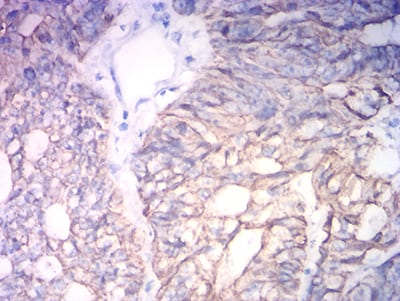

分类: 科研抗体货号: 31757别名: K18; CK-18; CYK18应用: WB,IHC,IF,FCM反应种属: Human